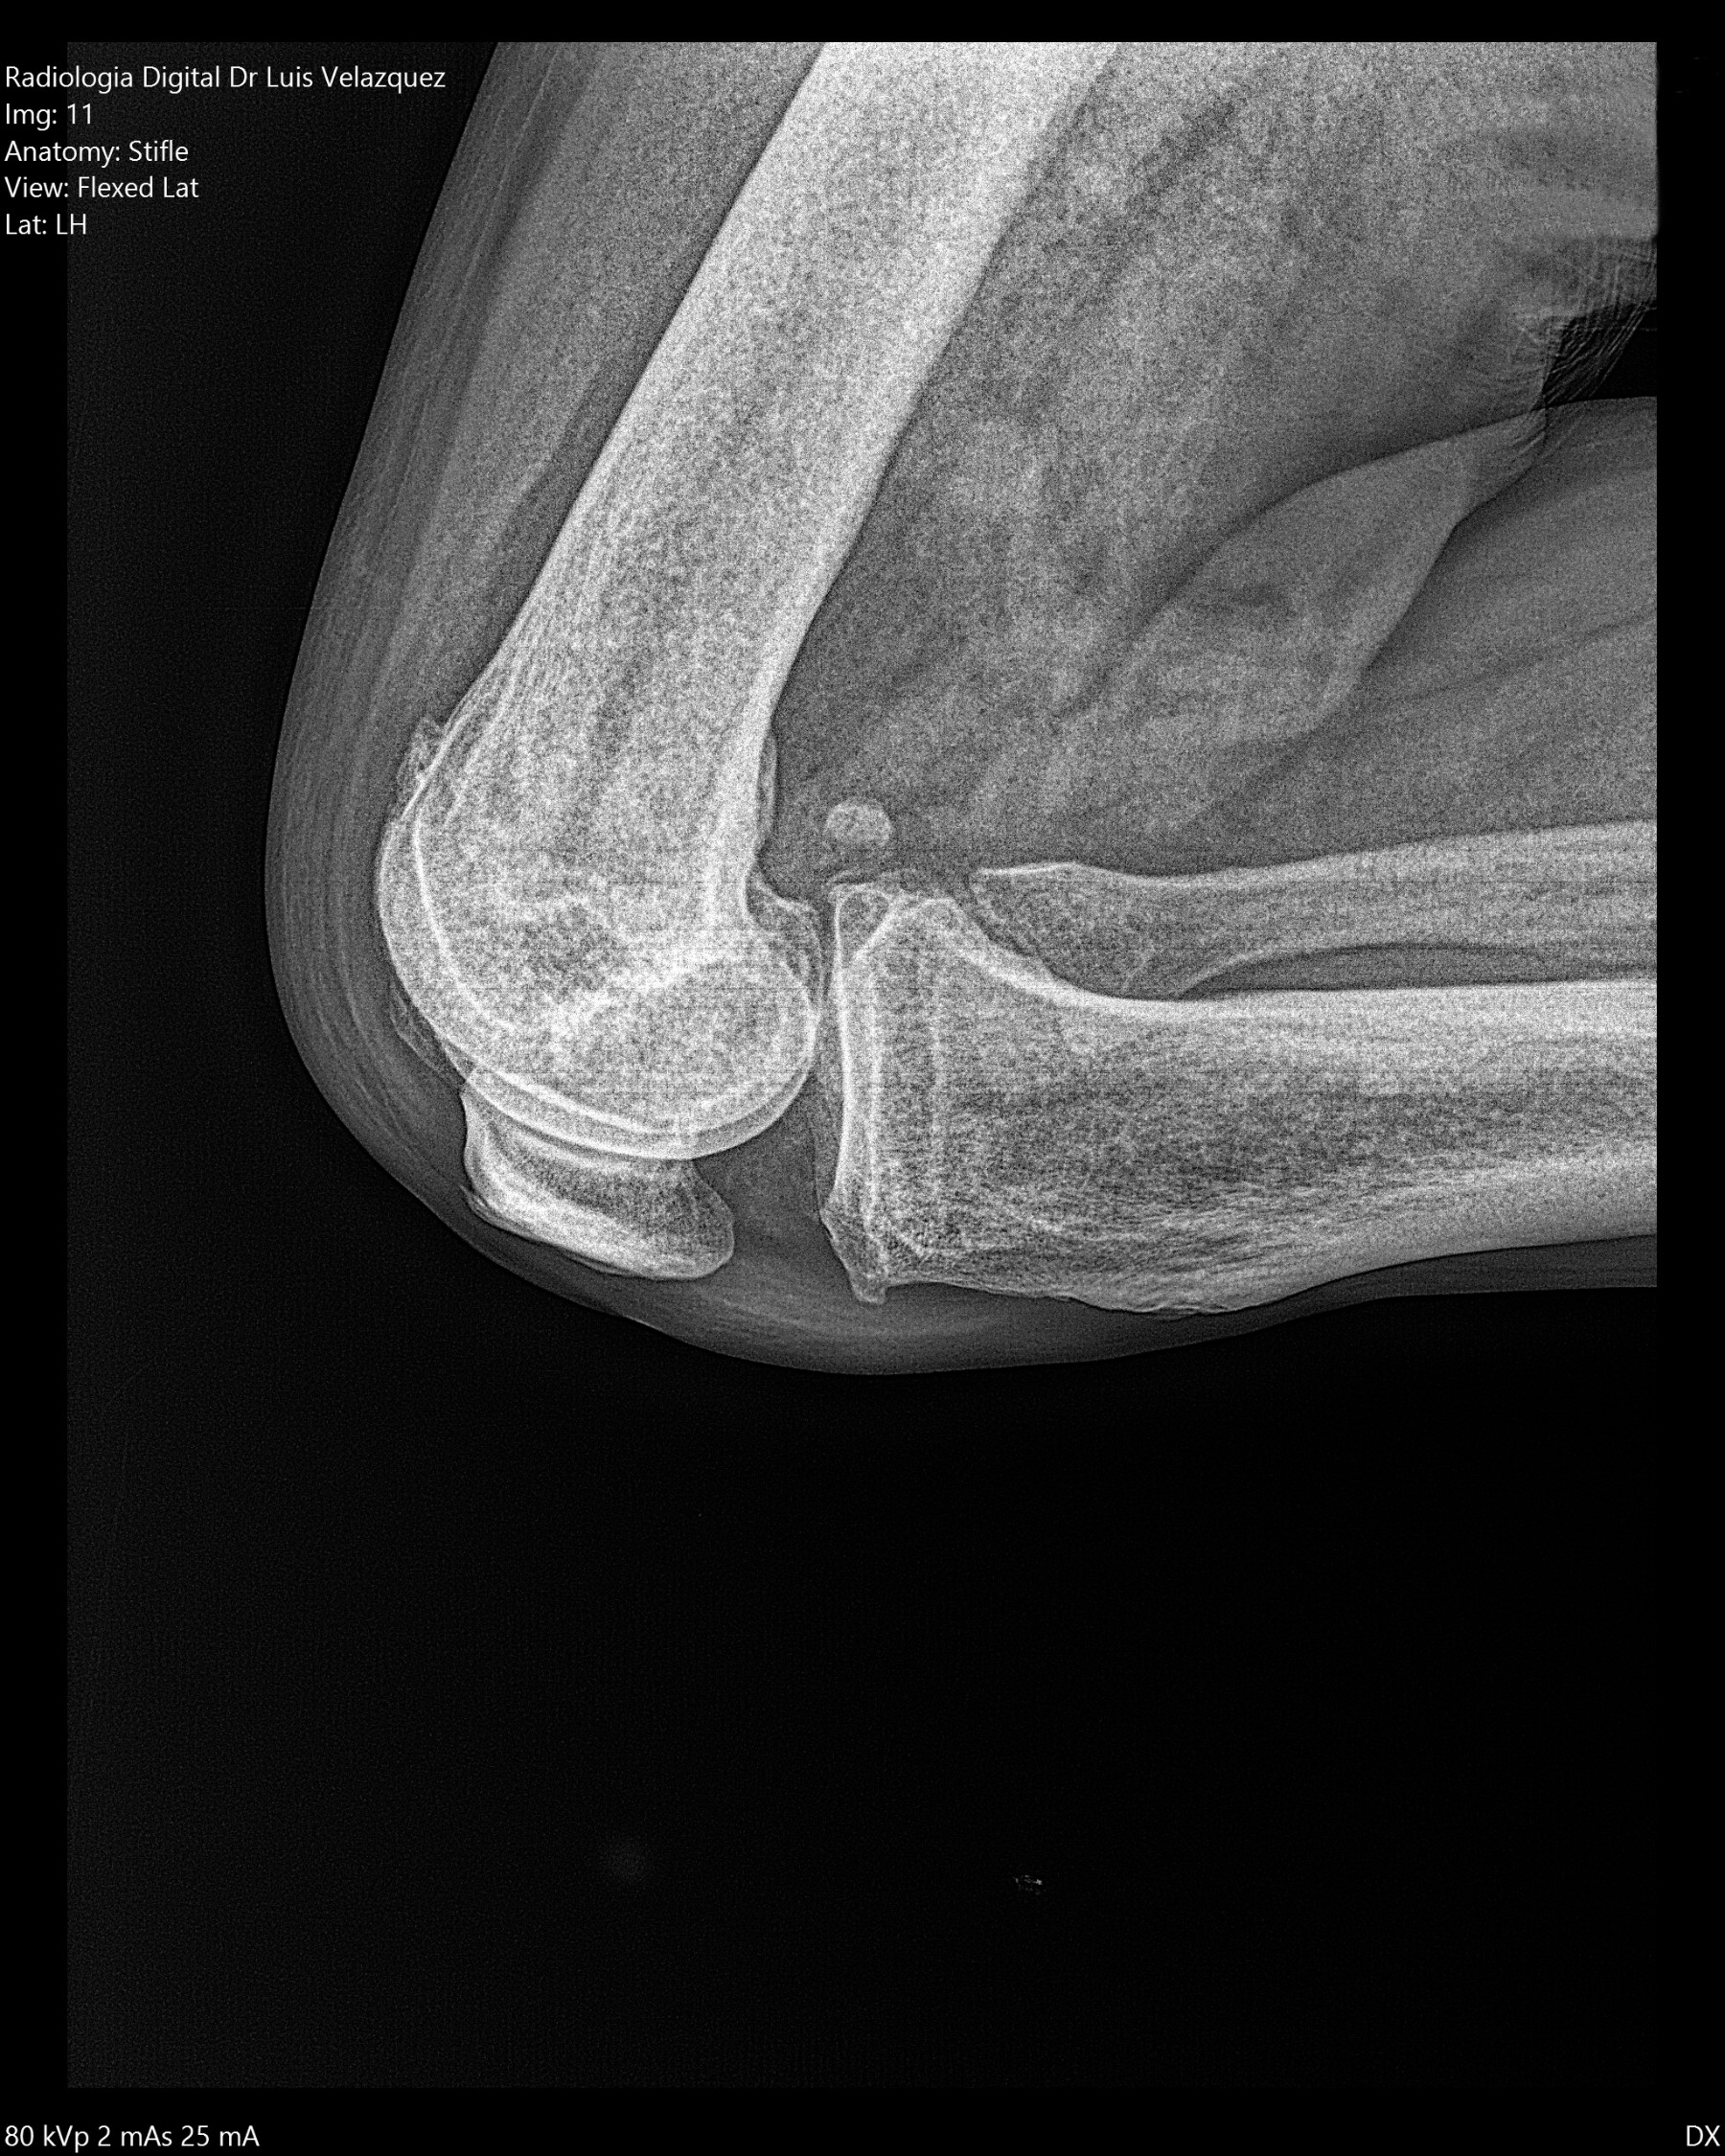

Radiología Digital como Herramienta Complementaria en el Dictamen de Bienes Muebles